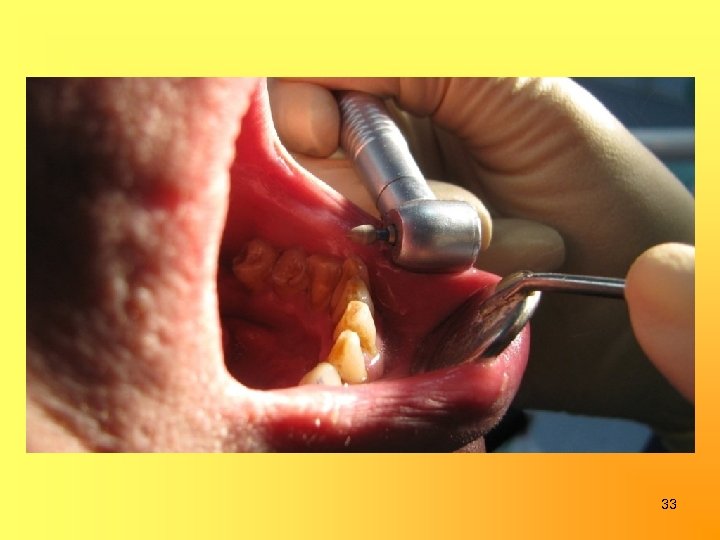

Избирательное пришлифовывание 32

33